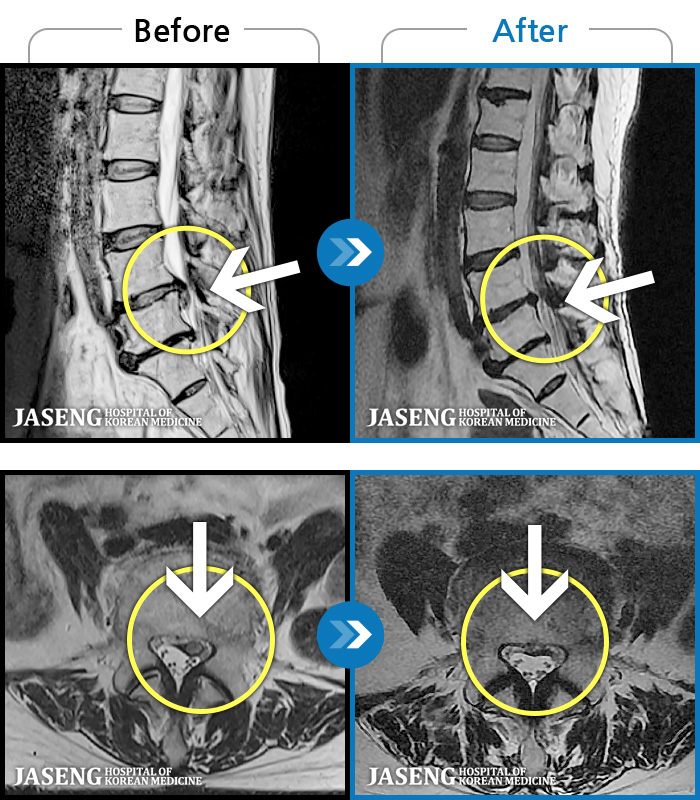

- MRI ġ

MRI ġ

1,301 MRI ũ ʸ Ȯϼ.